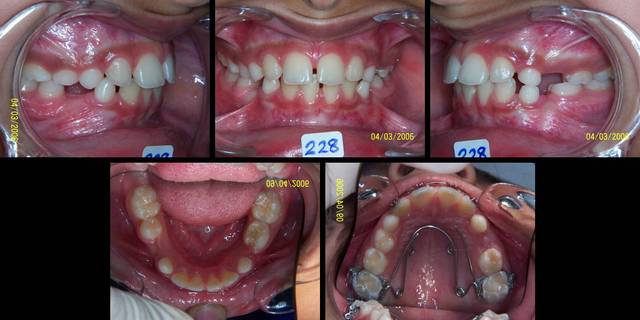

Voici un cas qui ressemble un peu a ton cas, en moins grave, mais qui peut te donner une idee sur ce qu'il faut faire.

Mon patient, ou plutot les parents, n'etaient pas tres cooperants, manquaient pas mal de RDV, et je n'ai plus revu a la fin de traitement. Ici a Abu Dhabi il en a pas mal comme ca!!

Bref, le systeme de MacAndrews peut etre utile dans ces cas. Un arc de base de stabilisation basic, jambe du cote de la deviation contre la laterale, le cote oppose est a distance pour permettre le mouvement des 4 incisives. Une boucle au milieu du pont lateral sert de stop pour le ressort active de la quantite de deplacement desiree avec 3 mm de plus et insere pendant la fabrication de l'arc de base. On laisse faire le systeme tout seul.